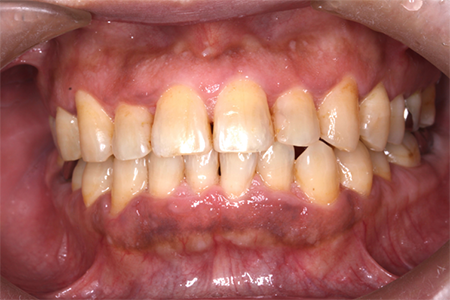

奥歯があることで前歯の負担を減らし、前歯を失うリスクを下げることが出来ます。